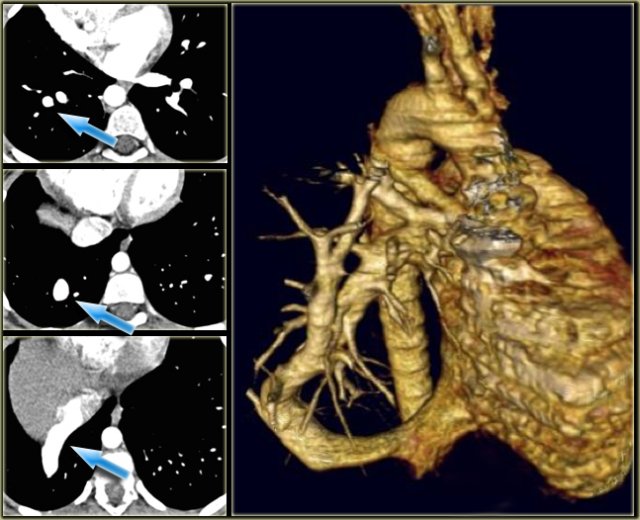

Coronal MPR (left), external volume rendering (middle) and internal volume rendering. Coronal MPR (left), external volume rendering (middle) and internal volume rendering.

Post-processing

Multiplanar reconstructions (MPR), volume rendered techniques (VRT) and maximum intensity (MIP) are very helpful.

There is no role for shaded surface or mini-IP's.

On the left an external and internal rendering which provides in contrast to MPR real 3D information.

In volume rendering the posterior view is preferred to get a good look at the arch and descending aorta.

Thick slab maximal intensity projection to study the pulmonary vasculature. Thick slab maximal intensity projection to study the pulmonary vasculature.

If you want to study peripheral vessels you will need thick slab maximal intensity projections.

For instance if you study arteriovenous malformations or discrepancy in lung flow.

Thick slab coronal maximal intensity projection image in patient with scimitar syndrome. Thick slab coronal maximal intensity projection image in patient with scimitar syndrome.

Notice that on the coronal MIP you can nicely see the difference in vascularization of the lungs with hypovascularity on the right in a patient with scimitar syndrome.

High grade coarctation of aorta not seen on axial images but clearly visualized on sagittal MPR. High grade coarctation of aorta not seen on axial images but clearly visualized on sagittal MPR.

3D reconstructions are helpful when there are short focal lesions like coarctation or when vessels course obliquely (figure).

Adding 3D reconstructions to axial images will increase the sensitivity from 90% to 100% (Lee, Siegel AJR 182:777-784 )

On the left a 17-day old boy with minimal cyanosis, mild heart failure and upper extremity hypertension.

On axial images you will have trouble diagnosis coarctation, because it is focal and in the same plane as the axial image.